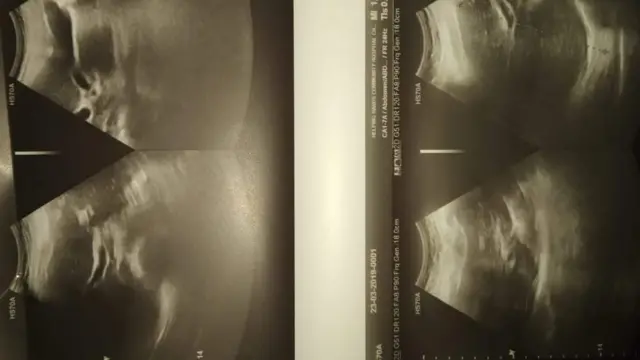

वि.सं. २०७५ असारमा जन्मिएका बालकलाई उपचारमा संलग्न स्वास्थ्यकर्मीहरूको "गल्ती"ले सिटामोलको गलत मात्रा धेरै दिइएका कारण र उपचारमा लापरवाही भएका कारण उनको स्वास्थ्यमा गम्भीर समस्या भएको बालकका अभिभावकको गुनासो छ।

चार वर्ष पुग्न लागेका रिहान न्यौपानेको अहिले पनि स्वास्थ्य अवस्था जटिल छ।